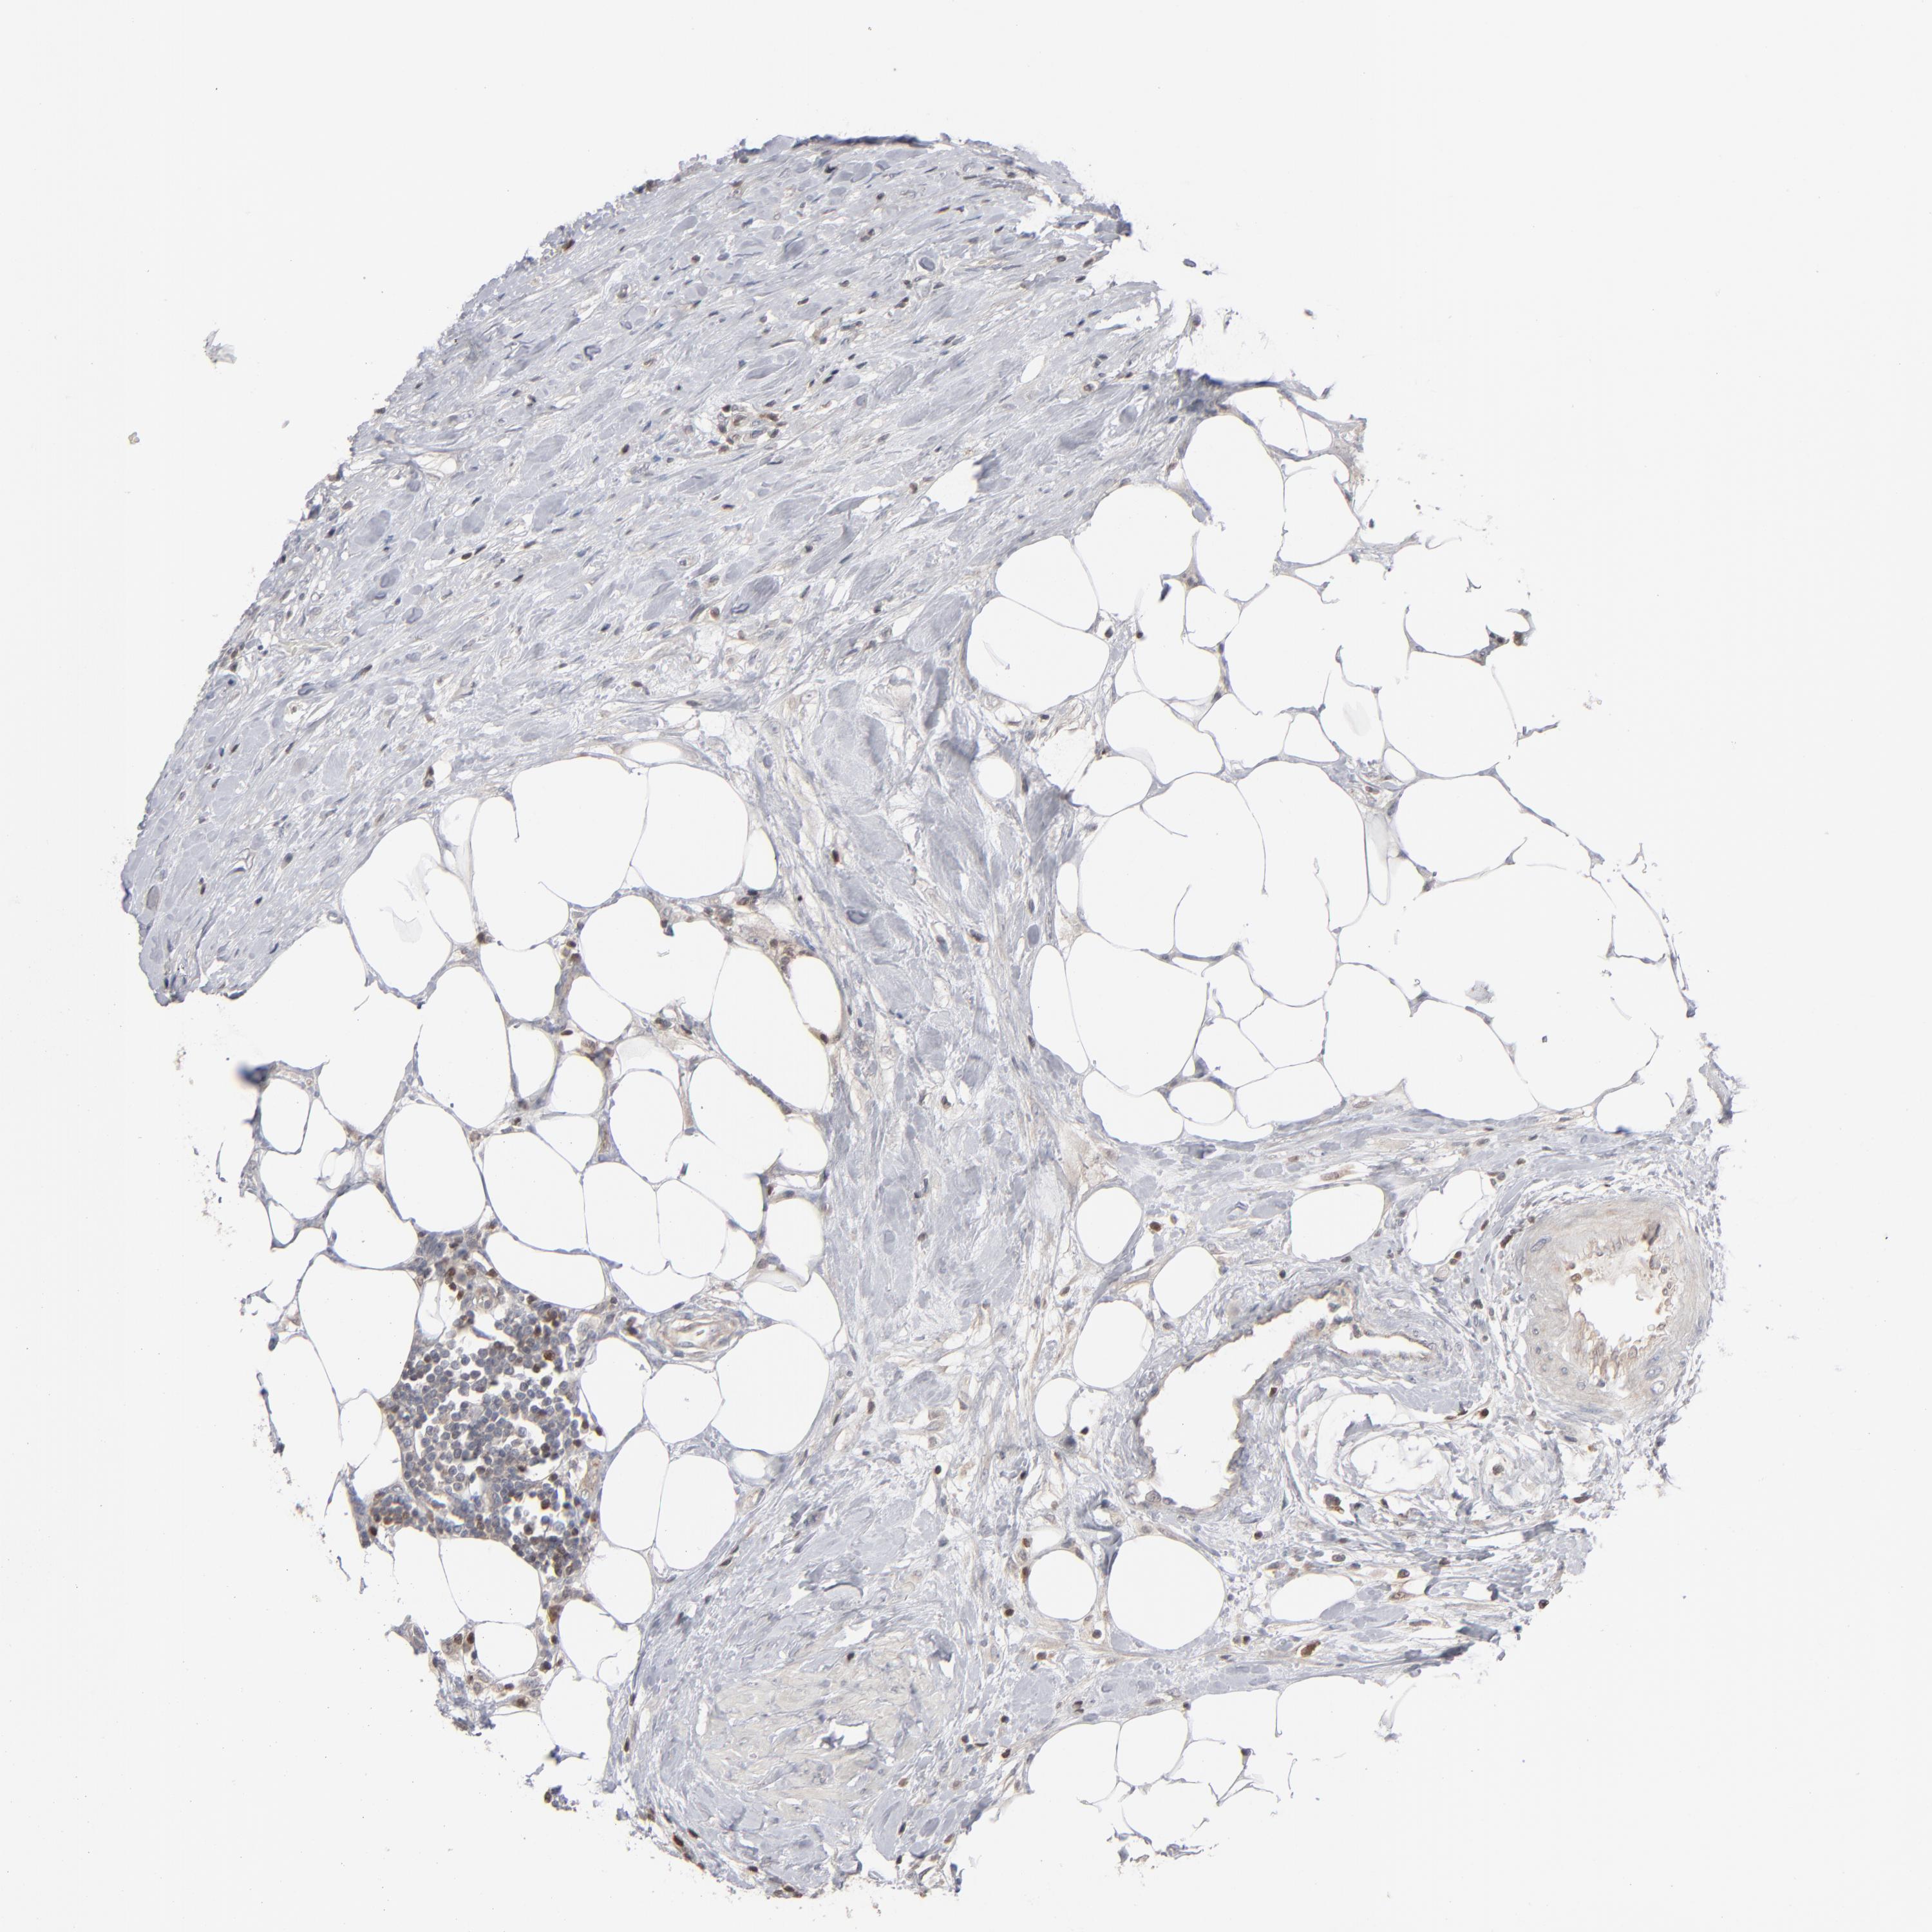

UROTHELIAL CANCER - Protein expressioni

A mouse-over function shows sample information and annotation data. Click on an image to view it in a full screen mode. Samples can be filtered based on level of antibody staining by selecting one or several of the following categories: high, medium, low and not detected. The assay and annotation is described here.

Note that samples used for immunohistochemistry by the Human Protein Atlas do not correspond to samples in the TCGA dataset.

Antibody stainingi

Antibody staining in the annotated cell types in the current human tissue is reported as not detected, low, medium, or high, based on conventional immunohistochemistry profiling in selected tissues. This score is based on the combination of the staining intensity and fraction of stained cells.

Each image is clickable and will lead to virtual microscopy that enables deeper exploration of all samples and also displays staining intensity scores, fraction scores and subcellular localization as well as patient and tissue information for each sample.

Antibody HPA001860

Antibody CAB013108

Urothelial carcinoma, High grade

Urothelial carcinoma, Low grade